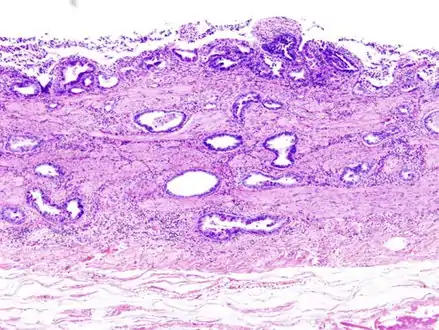

Most tumors are adenocarcinomas, with a small percent being squamous cell carcinomas.